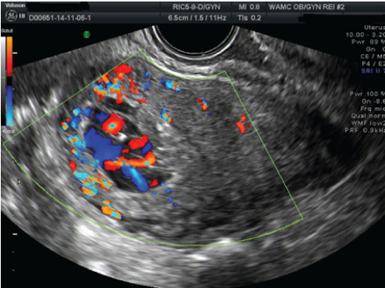

- TVUS: ohne Farbdoppler als tubuläre oder schwammige, echoleere bis hypoechogene Bereiche im Myometrium, verdicktes Myometrium

- Farb- und Spektraldoppler: erhöhte Flussgeschwindigkeit im Niederdruckgefässsystem (RI 0.25-0.55), verminderte Pulsatilität und erhöhte Flussgeschwindigkeit der Aa. Uterinae

Bild 1: Sonographisch hypervaskularisierter Befund in Uterus (3)